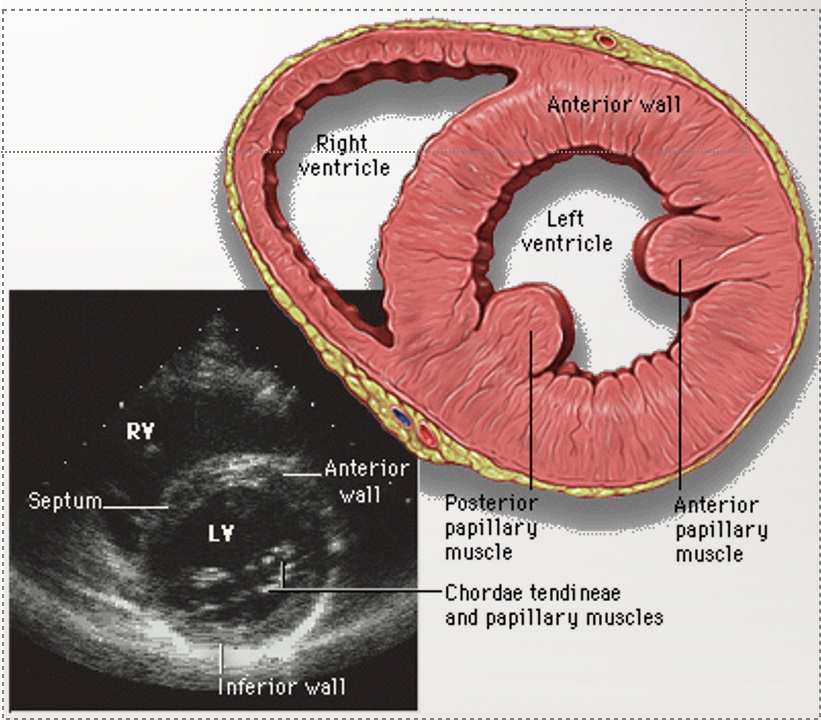

Identify structures and the view of this echo

PSAX